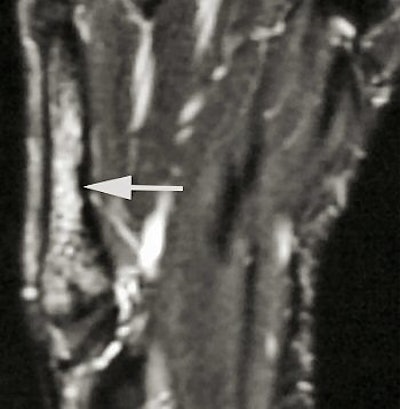

| MRI shows bone marrow edema at the base of the fifth metatarsal. All images courtesy of Duke University Medical Center, Durham, NC. |

The first study was led by Dr. Joseph Guettler, now an orthopedic surgeon at William Beaumont Hospital in Royal Oak, MI. It revealed that the greatest load on the fifth metatarsal occurred from pivot moves during a forward sprint, and it challenged the long-held but scientifically unfounded notion that high arches contribute to foot injuries.

Counter to shoe manufacturers' assumptions, the study showed that arch support seems to shift stresses away from the fifth metatarsal ("Fifth Metatarsal Stress Fractures in Elite Basketball Players: Evaluation of Forces Acting on the Fifth Metatarsal," American Academy of Orthopedic Surgery meeting, March 13, 2004).

The follow-up study was led by Dr. Nancy Major, associate professor of radiology at Duke University Medical Center's musculoskeletal division. Her study determined that MRI can effectively predict metatarsal stress fractures by depicting bone marrow edema (a precursor to fractures), thereby enabling the prevention of potential fractures with the use of orthotics.

In this study, 26 male basketball players from Duke and North Carolina Central University in Durham were imaged before and after their 2003 season. Although 19 of 52 feet showed abnormalities with MRI, only one player had complaints of a symptomatic midfoot. The use of an orthotic provided immediate relief, and the player did not subsequently develop stress fractures.